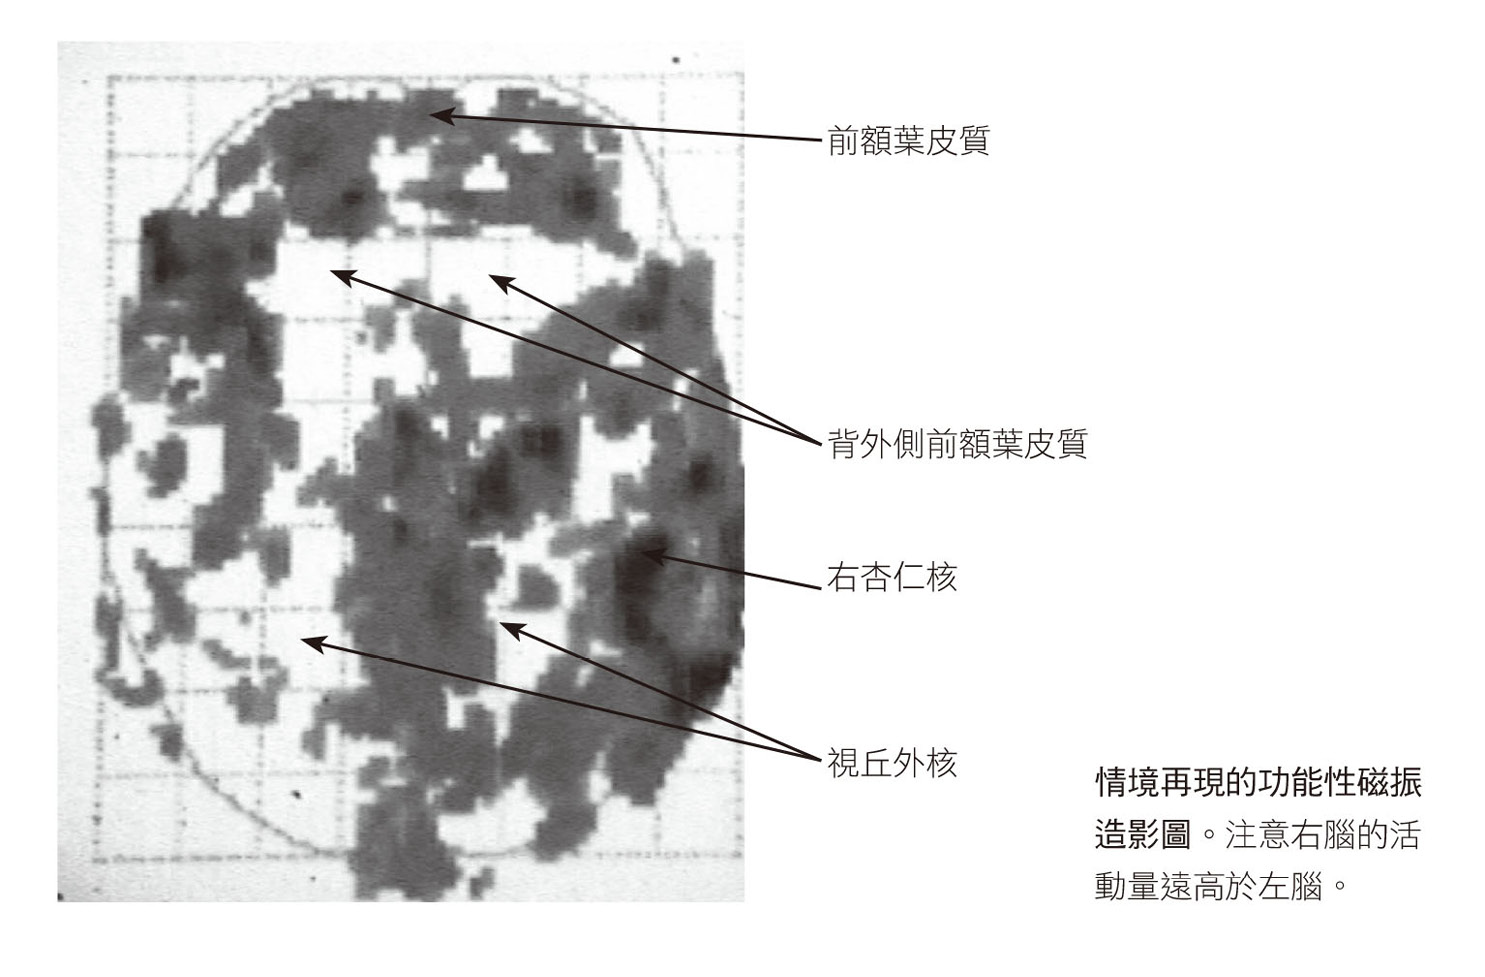

八位受試者都完成實驗之後,史考特.羅許和數學專家及統計學者比較腦部在情境再現與接受中性刺激時的活化狀態,製作出合成影像,幾個星期後,他將結果寄給我,如下圖所示。我把這些腦部影像圖貼在廚房冰箱上,接下來幾個月每晚都盯著看,早年天文學家透過望遠鏡看到新的星座時,大概就像我這樣吧。

影像圖上有一些令人費解的點和顏色,但活化程度最大的區域並不讓人意外,正是腦部中央偏右下方一個紅色的大區塊,即邊緣區,或稱情緒腦。目前已知強烈的情緒會活化邊緣系統,尤其是名為杏仁核的區域。杏仁核會在危險逼近時發出警告,並啟動身體的壓力反應。我們的研究清楚顯示,遭受創傷的人一旦接觸跟自己的特定經驗有關的影像、聲音或想法,如瑪莎的案例,即使事件已過了十三年,杏仁核都會發出警報。這個恐懼中樞被活化後會釋放壓力荷爾蒙和神經衝動,促使血壓上升、心跳加快,以及增加氧氣吸收,讓身體做好戰或逃的準備。1即使瑪莎很清楚自己正安靜地躺在掃瞄儀裡,但繫在手臂上的監測器仍記錄到這個狂亂激發的生理狀態。

● 無法言喻的恐懼

最出乎我們意料的發現,是左額葉一個稱為布洛卡區的白點,此處的顏色改變意味著這個腦區的活動量顯著下降。布洛卡區是腦部的語言中樞之一,中風病人的這個部位常因血液供給中斷而受到影響。布洛卡區功能異常,你就無法將想法和感受訴諸於語言或文字。影像圖顯示,創傷情境一再現,布洛卡區就會「斷線」,換言之,這些證據顯示創傷對大腦造成的生理損害不亞於中風,甚至可能有部分還雷同。

語言失效時,揮之不去的影像便佔據這段經驗,以噩夢和情境再現的形式一再出現。從受試者的腦影像圖可以發現,相對於布洛卡區的不活化,布羅德曼十九區會亮起,這區域位於視覺皮質,外界圖像進入大腦後會先被送到這裡暫存。我們對於這個腦區在創傷事件發生很久之後仍會活化感到驚訝,因為正常情況下,原始圖像送到十九區後就會立刻分散到大腦皮質的其他部位,好讓我們詮釋所見事物的意義。但如今我們親眼目睹受試者這一個腦區又亮了起來,彷彿創傷正在實際發生。

● 偏向大腦的一側

影像圖也顯示當受試者經歷情境再現時,只有右側大腦亮起來。目前有許多科學文獻和大眾讀物提到左、右腦的不同。一九九○年代早期,我聽說有些人開始把人類分為左腦人(理性、有邏輯的人)和右腦人(重視直覺、有藝術天分的人),我不是很在意這種說法,然而我們的掃瞄結果清楚顯示,過去的創傷影像會使右腦活化,左腦不活化。

我們現在知道大腦的兩半球說著不同的語言,右腦使用直覺、情緒、視覺、空間和觸覺,左腦則是語文、次序和分析。左腦總是在說話,右腦則傳遞生命的樂曲,透過臉部表情、肢體語言,以及在歌唱、咒罵、哭泣、跳舞或模仿時所發出的愛與愁的聲音來交流。右腦是嬰兒在子宮中最早發育的部位,讓母親和胎兒能做非語言的溝通。左腦則在幼兒開始理解和學習說話時才上線,使幼兒能說出事物的名字,比較事物、瞭解事物之間的相互關係,並且開始向別人表達自己獨特、主觀的經驗。

左、右腦也以截然不同的方式處理我們過往的經歷。2左腦會記住事件中的事實、數據和詞彙。我們用左腦來解釋並整理經驗。右腦儲存對聲音、觸覺和氣味的記憶,以及這些記憶引發的情緒,會對過去經驗中的聲音、臉部特徵、姿勢和地點產生自動化反應。右腦喚回的東西就像是憑直覺得知的真相,也就是事物的本質。即使只是向朋友細數愛人的優點,我們的感情也會因為她的臉孔令我們想起四歲時喜歡的那位阿姨而深深顫動。3 一般情形下,左、右腦大致上是互相合作的,就算這個人被認為傾向某一側的腦也一樣。然而,如果其中一邊停擺(即使只是暫時性的),或被完全切除(如早期的腦部手術),就會導致大腦功能障礙。

左腦不活化,會直接影響我們將經驗組織成邏輯順序的能力,以及將多變的感受與知覺轉譯為文字的能力(左腦的布洛卡區會在情境再現時暗下來)。沒有了順序,我們就無法確認因果關係、預測行為的長期後果,或為將來做完整的規畫。極度沮喪、不安的人有時會感覺自己正「失去理智」,用專業術語來說,他們正在經歷執行功能喪失。

當某個事物令受創者回想起過去,他們右腦的反應會猶如創傷事件正在此刻發生,但由於他們的左腦此時無法妥善運作,因此他們或許不會意識到自己正在重新經驗創傷和重演過往,而只是暴怒、害怕、氣憤、羞愧或呆住。等情緒風暴過去後,他們可能會遷怒於某件事或某個人,認為他們會做出這種舉動,都是因為你遲到十分鐘,因為你烤焦了馬鈴薯,或是因為你「從來都不聽我說話」。當然,我們大多數人有時也會這樣,但當我們冷靜下來,或許會承認是自己的錯誤,然而,創傷卻阻礙了這種覺察能力,經過多年研究,我們找到了其中的原因。

史登的腦部掃瞄顯示情境再現正在發生,腦中再次經歷創傷時就像這樣:右下方亮起,左下方暗掉,以及中心附近四個對稱的空白(你或許已經認出它與第三章哈佛研究提到的亮起的杏仁核與離線的左腦極為類似)。史登的杏仁核沒有區別過去與現在,活化的情形彷彿車禍就發生在掃瞄儀內,並激發了強烈的壓力荷爾蒙和神經系統的反應,造成他冒汗、顫抖、心跳加速、血壓升高。當一輛卡車撞上你的車子時,這些反應完全正常,且可能救你一命。

高效能的煙霧偵測器非常重要,因為你絕對不想被突然的烈火困住。但如果每次聞到煙味就發狂,會導致極大的混亂。是的,你需要偵測出別人是否在生你的氣,但如果你的杏仁核過度敏感,你可能習慣性地害怕別人討厭你,或覺得別人都在害你。

史登和烏妲在車禍後都變得過度敏感又焦躁不安,這表示兩人的前額葉皮質在面對壓力時很難保持控制。史登的情境再現還引發更嚴重的反應。

大腦前方有兩個白色區域(下圖的上方),就是左、右腦的背外側前額葉皮質,這兩區若不活化,人會失去時間感,被困在某一刻,感覺不到過去、現在與未來。16

大腦有兩個系統與創傷的心理歷程有關,處理的分別是情緒的強度和脈絡。情緒的強度由煙霧偵測器(杏仁核)和其對手瞭望臺(內側前額葉皮質)共同決定,而某個經驗的脈絡與意義則由背外側前額葉皮質與海馬迴來決定。背外側前額葉皮質位於前腦的外側,而內側前額葉皮質則位於中間。大腦中線附近的結構負責處理你的內在經驗,大腦外側的結構則主要負責你和周遭環境的關係。

背外側前額葉皮質告訴我們,現在的經驗如何與過去相連、會如何影響將來,你可以將之視為腦中的計時器。知道凡事皆有其極限,遲早都會結束,這讓許多經驗都變得可以忍受。相反地,如果某些情況好似永無止境,就會變得難以忍受。我們大多數人都從個人的悲傷經驗得知,極度的哀慟通常會伴隨著一種感受:這個悲慘的狀態會一直持續下去,我們永遠無法從傷害中復原。創傷就是「這會永遠持續下去」的極端經驗。